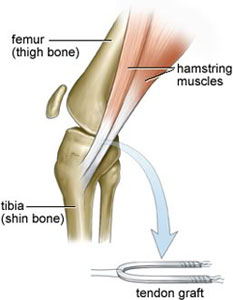

The most common autograft options are bone-patellar-bone tendon and hamstrings. ACL Reconstruction Surgery is typically done as an outpatient procedure. Depending on graft choice, open incisions may be necessary to harvest the tissue that is to be used as the new ACL. Knee Arthroscopy is then performed to inspect the Knee, treat additional injuries (meniscus tears or cartilage damage), and to prepare the Knee for the new ACL.

Once the graft tissue has been prepared and the torn ACL tissue has been removed, the surgeon is ready to place the ligament within the Knee. Small tunnels (7-10 mm) are drilled in the tibia and femur to allow the ligament to be pulled up into the Knee.

Accurate placement of these tunnels is critical to successful ACL Reconstruction Surgery. After the ACL graft is in position, fixation devices (screws, washers, buttons, etc.) get used to keep it there until it can heal into its place.

Surgical steps:

- The graft which gets used for reconstruction, is harvested and prepared for the replacement. Usually the patellar tendon or the Semitendinosis and Gracilis tendon autografts are used in athletes.

- After harvesting the tissue, a hole is drilled from the front of tibia diagonally into the Knee and ends up where the ACL attaches to the top of the shin. Next, the orthopaedic surgeon drills a hole in femur at the anatomical foot-print on the lateral femoral condyle.

- The harvested replacement graft pulled into place through the holes which were just drilled and locked after flipping the Endo-CL Button.

- The new ligament is then held into place by two bio-absorbable screws or metallic screws.

Graft Harvesting

Graft Preparation

Final Fixation

In this procedure, rather than using the patellar tendon, the surgeon uses the patient's own hamstring tendon, either the Semitendinosus and Gracilis tendons from the same leg.